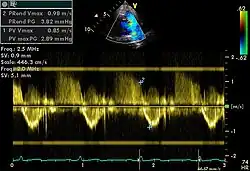

Doppler

Spectral doppler

Spectral doppler is presented similarly to M-mode in which the doppler information is plotted as a spectrogram. This can be both "continuous" and "pulse" wave where the former shows the spectrum along a specific line and the latter shows within a small window along that line. Continuous wave is better at showing maximal velocities and pulse wave is better for showing flow through a small volume.

Spectral doppler is often used for quantification of flow. For example, the aortic valve area can be estimated using the continuity equation by measuring the velocity time integral (VTI) of the aortic valve & LV outflow tract; the VTI is calculated by tracing the flow on the spectral doppler curve. Spectral doppler is also useful for calculating the maximum flow and mean flow through a valve (used to grade valve stenosis).